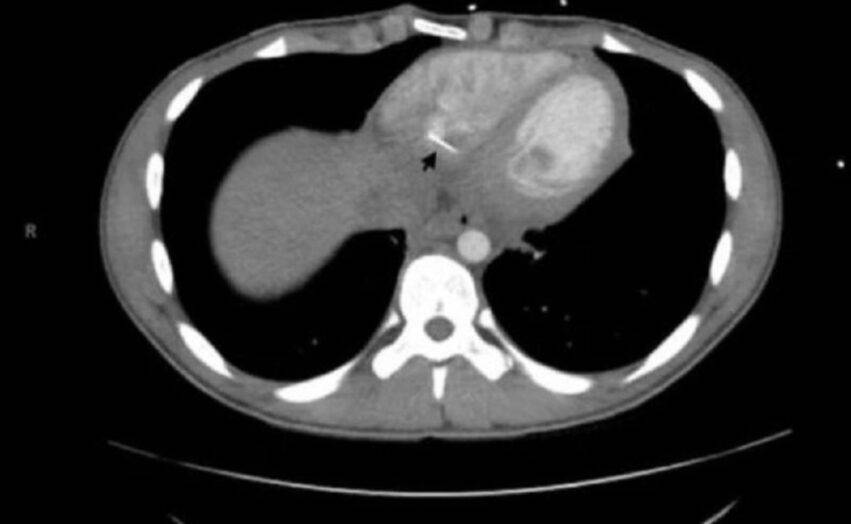

Successivamente però, i medici hanno scoperto qualcosa di sorprendente grazie a una scan. Nel suo cuore c’era un corpo estraneo. L’oggetto era lungo 3,5 cm. e sporgeva dal ventricolo destro. Inizialmente il giovane ha spiegato che non ricordava di aver ingerito alcun corpo estraneo o di aver subito un trauma al petto. A questo proposito ricordiamo la vicenda di un bambino che aveva ingerito una batteria.

I dottori hanno dovuto operarlo al cuore per estrarre l’ago che metteva seriamente a repentaglio la sua vita. In precedenza sono stati trovati oggetti nel cuore, ma si tratta di casi rari, specialmente nei bambini e negli adolescenti. Infine il caso potrebbe portare a nuovi modi di trattare gli oggetti taglienti che vengono ingeriti. A proposito di oggetti ingoiati un bambino di 1 anno tempo fa è morto a causa di una pallina.